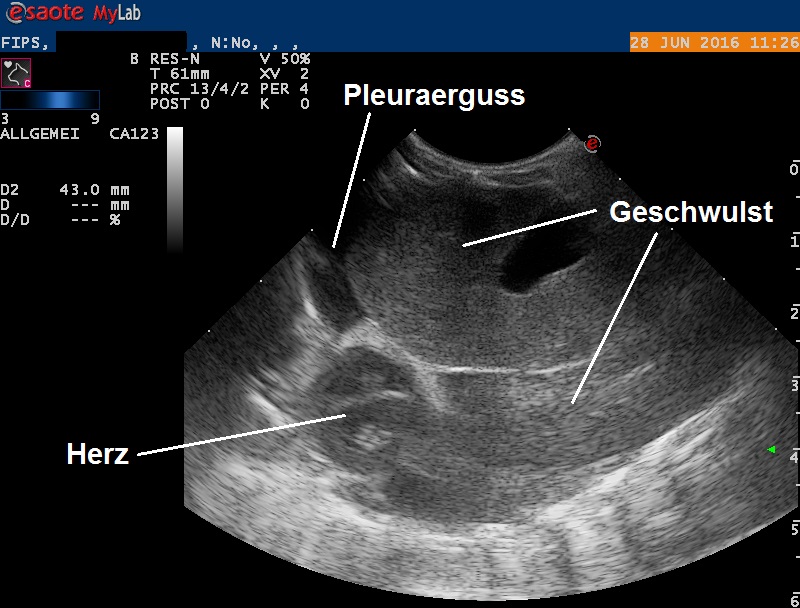

Da dieser beidseitig aufgetretene Exophtalmus nicht schlüssig erklärt werden kann, wird die Nagermedizin-Literatur konsultiert. In zwei Standartwerken ist das Problem nicht erwähnt, erst eine Internetrecherche weckt den Verdacht, dass das Problem durch einen Bluthochdruck bedingt sein könnte, welcher den Exophtalmos bewirken kann. Ein Bruströntgen zeigt denn auch einen grossen Schatten, welcher entweder durch ein stark vergrössertes Herz oder aber einen Tumor im Brustkorb hervorgerufen sein könnte. Ein Ultraschall zeigt dann, dass es sich beim Schatten tatsächlich um eine grosse Geschwulst handelt, welche im vorderen Teil des Brustkorbes entspringt, die Lunge verdrängt und auch etwas Flüssigkeitsbildung zwischen Lunge und Brustkorb (Pleuraerguss) provoziert hat. Trotz der starken Verkleinerung des Lungenvolumens zeigt das Tier aber keine Atemnot.